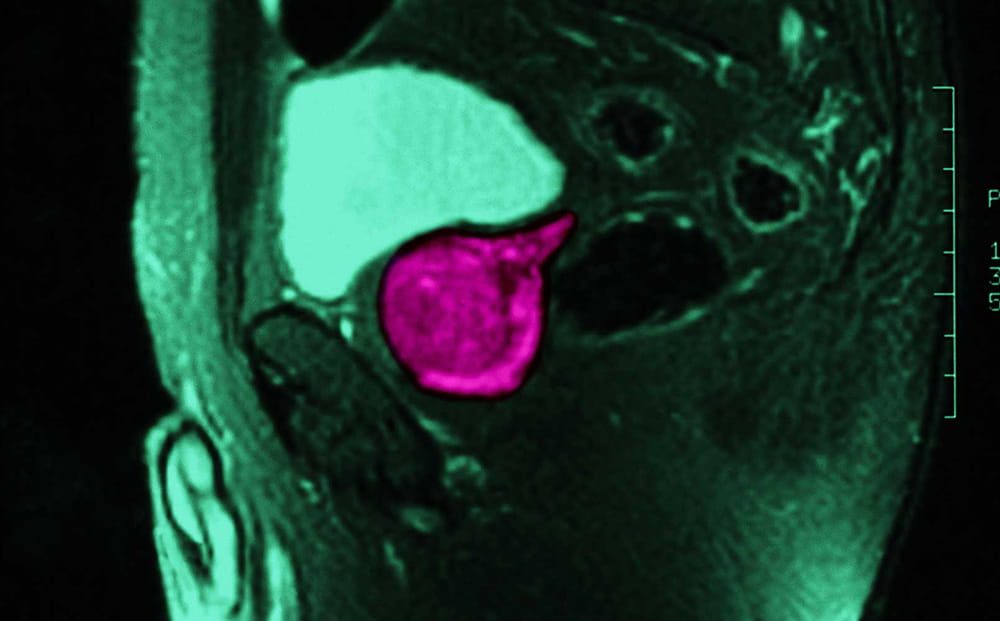

MRI of prostate

Supported by a National Institutes of Health (NIH) grant, our team played an important role in a unique discovery that is now available to patients at University across Northeast Ohio. Dr. Lee Ponsky and his team developed a combined quantitative MRI and computerized decision support exam for more accurate detection and grading of prostate cancer both in the peripheral and transitional zones. It’s just one of the ways University Hospitals is researching, developing and delivering new and advanced patient care with these MRIs for prostate cancer screening.